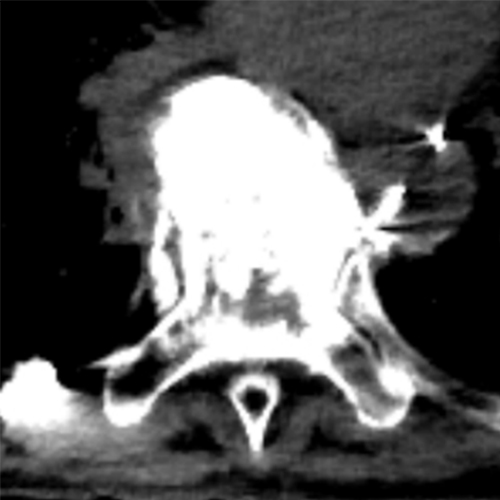

椎体腫瘍術前塞栓時に用いるsubtraction CTAに関する研究

椎体に発生・転移した腫瘍による脊髄圧迫あるいは切迫状態を生じた場合、整形外科医により椎体固定術が行われることがありますが、術中出血量を減少させるために当科へ椎体腫瘍術前塞栓を依頼されることがあります。栄養血管分岐が疑われる血管の選択後にCTAを撮影していますが、造骨性転移や骨棘形成の強い症例では、造影効果と骨硬化が判別しにくく、その血管が本当に腫瘍に関与しているか苦慮していました。Subtraction CTA(単純CTとCTAで差分を作成し、濃染域のみを描出する)を作成することで、濃染域と骨硬化を判別でき、過不足のない塞栓を行えることが期待されます。これらの有効性と安全性について臨床的に研究しています。